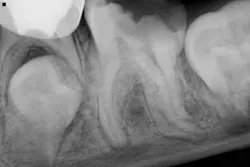

A 10-year-old male presents to have endodontic treatment on no. 19. He is asymptomatic currently, but he has a recent history of pain and slight swelling. Antibiotics were employed, and he is better now.

As can be seen radiographically, the tooth is fully matured apically. No. 18 is clearly present as is no. 20.